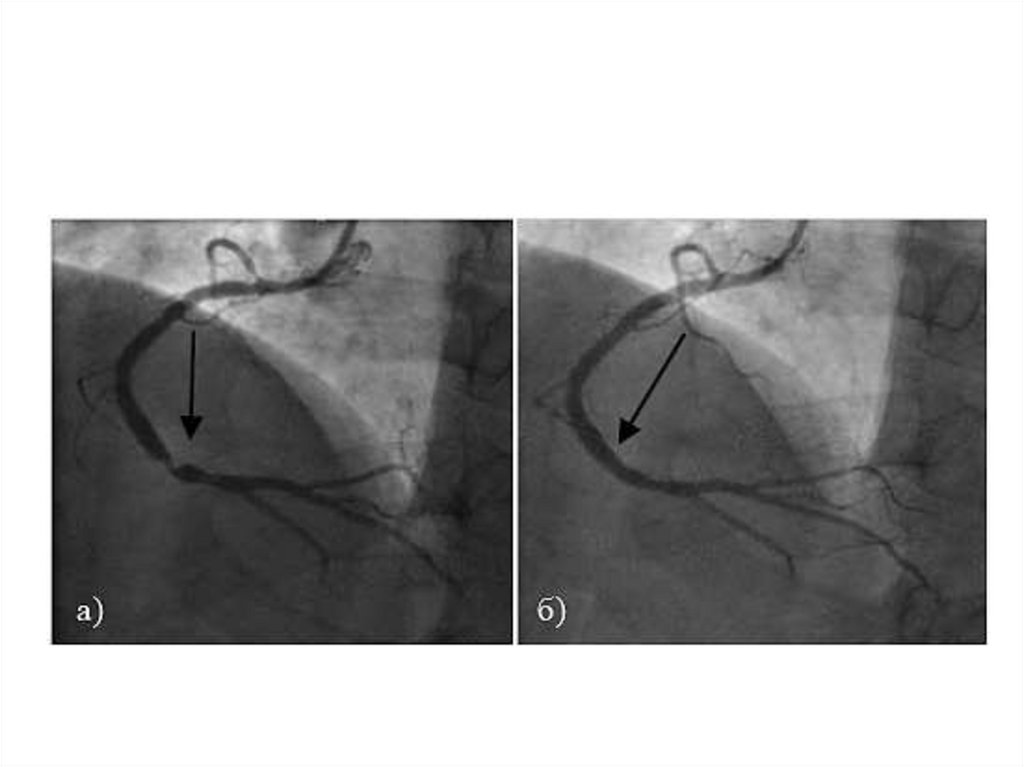

25.

ЭКГ при вазоспастической стенокардии

а – вне приступа

б - во время приступа